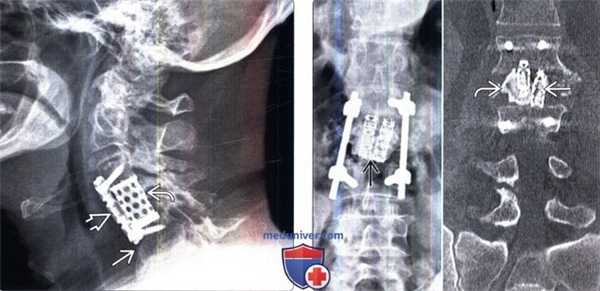

(Слева) Рентгенография в боковой проекции: случай взрывного перелома L2. Пациенту выполнена корпорэктомия и замещение тела позвонка телескопическим кейджем Synex и двусторонняя транспедикулярная стабилизация L1-L3. Задачами хирургического вмешательства при подобных повреждениях являются декомпрессия нервных образований, восстановление высоты тела позвонка, коррекция угловой деформации и стабилизация позвоночного столба.

(Справа) Рентгенография в прямой проекции: визуализируются ТК и боковая стабилизирующая конструкция, которые вкупе позволили добиться эффективной дистракции и восстановления высоты передней колонны, а также снизить стрессовые нагрузки, приходящие на задний транспедикулярный фиксатор.

(Слева) Рентгенография шейного отдела позвоночника в боковой проекции: случай корпорэктомии С4 с замещением тела позвонка кейджем и стабилизацией С3-С5 сегмента вентральной пластиной. Подобные сетчатые кейджи выбираются исходя из размеров замыкательных пластинок и высоты дефекта. На этом снимке видны признаки некоторого коллапса тела С5 с проседанием в дефект пластины и кейджа.

(Справа) На рентгенограмме в прямой проекции и фронтальном КТ-срезе визуализируются парные кейджи Pyramesh, использованные для реконструкции коллабированного тела L2 позвонка. Вокруг кейджей визуализируется метилметакрилат.

(Справа) Рентгенография в прямой проекции: визуализируются ТК и боковая стабилизирующая конструкция, которые вкупе позволили добиться эффективной дистракции и восстановления высоты передней колонны, а также снизить стрессовые нагрузки, приходящие на задний транспедикулярный фиксатор. (Слева) Рентгенография шейного отдела позвоночника в боковой проекции: случай корпорэктомии С4 с замещением тела позвонка кейджем и стабилизацией С3-С5 сегмента вентральной пластиной. Подобные сетчатые кейджи выбираются исходя из размеров замыкательных пластинок и высоты дефекта. На этом снимке видны признаки некоторого коллапса тела С5 с проседанием в дефект пластины и кейджа.